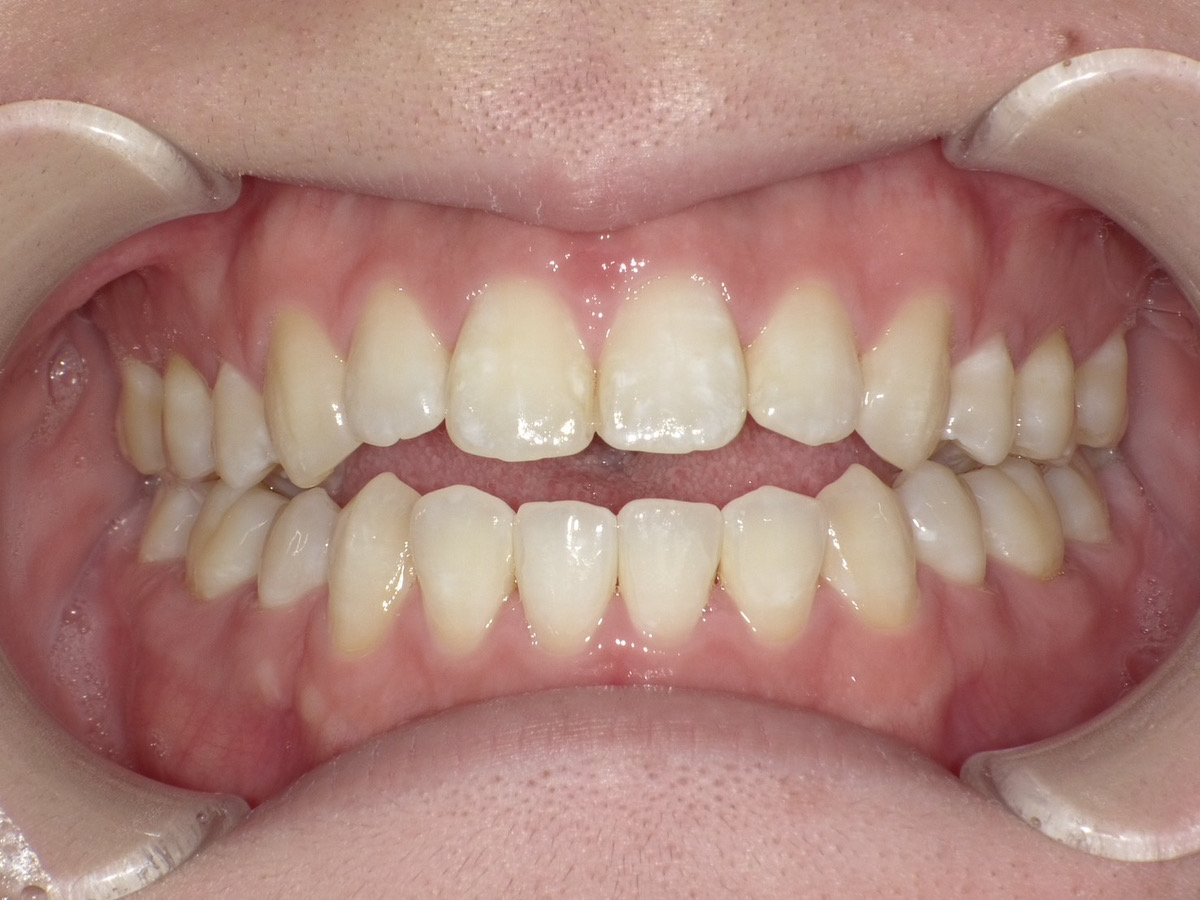

症例③

症例3_治療前 症例3_治療後

治療方法 マウスピース矯正

治療期間 1年8ヶ月

治療総額 850,000円

特記事項 抜歯なし

リスク・副作用 治療の初期段階では痛みや不快感が生じやすくなりますが、1週間前後で慣れます